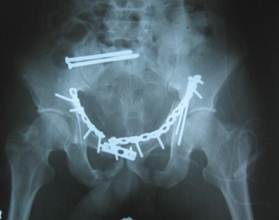

В большинстве случаев при переломах вертлужной впадины со смещением консервативными методами не удается добиться восстановления конгруэнтности суставных поверхностей. В таких случаях после обязательного тщательного предоперационного планирования на основе компьютерной томографии или объемной компьютерной реконструкции выполняют открытую репозицию с погружным остеосинтезом винтами или специальными реконструктивными пластинами (рис.15). При тяжелых разрушениях вертлужной впадины в сочетании с повреждениями головки бедренной кости выполняют тотальное эндопротезирование тазобедренного сустава.

![]() |

Рис.15. Рентгенография остеосинтеза винтами и реконструктивными пластинами по поводу разрыва крестцово-подвздошного сочленения справа, разрыва лонного симфиза, перелома дна вертлужной впадины с обеих сторон.